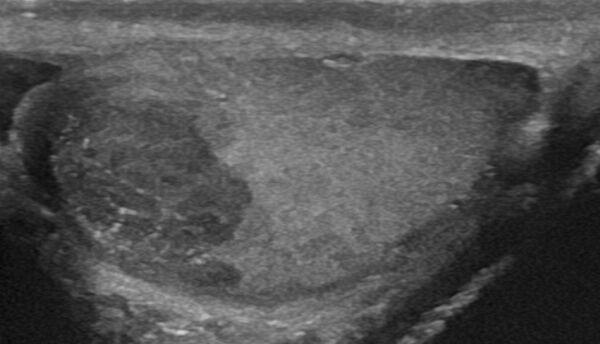

- Семинома (около 38%). Инвазивная злокачественная опухоль, построенная из герминогенного атипичного эпителия. Встречается наиболее часто, довольно рано даёт метастазы. Нередко сопровождается некрозами.[5] Поражает всё яичко, оставляя свободным только узкое кольцо нормальной ткани между опухолью и белочной оболочкой.[6]